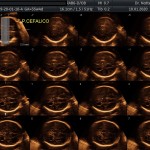

Los objetivos más importantes de esta ecografía son la evaluación de:

- La anatomía fetal: Diagnostico de Malformaciones Estructurales de aparición tardía (displasias esqueléticas, alteraciones cardíacas pequeñas, alteraciones de la vía urinaria y obstrucciones intestinales).